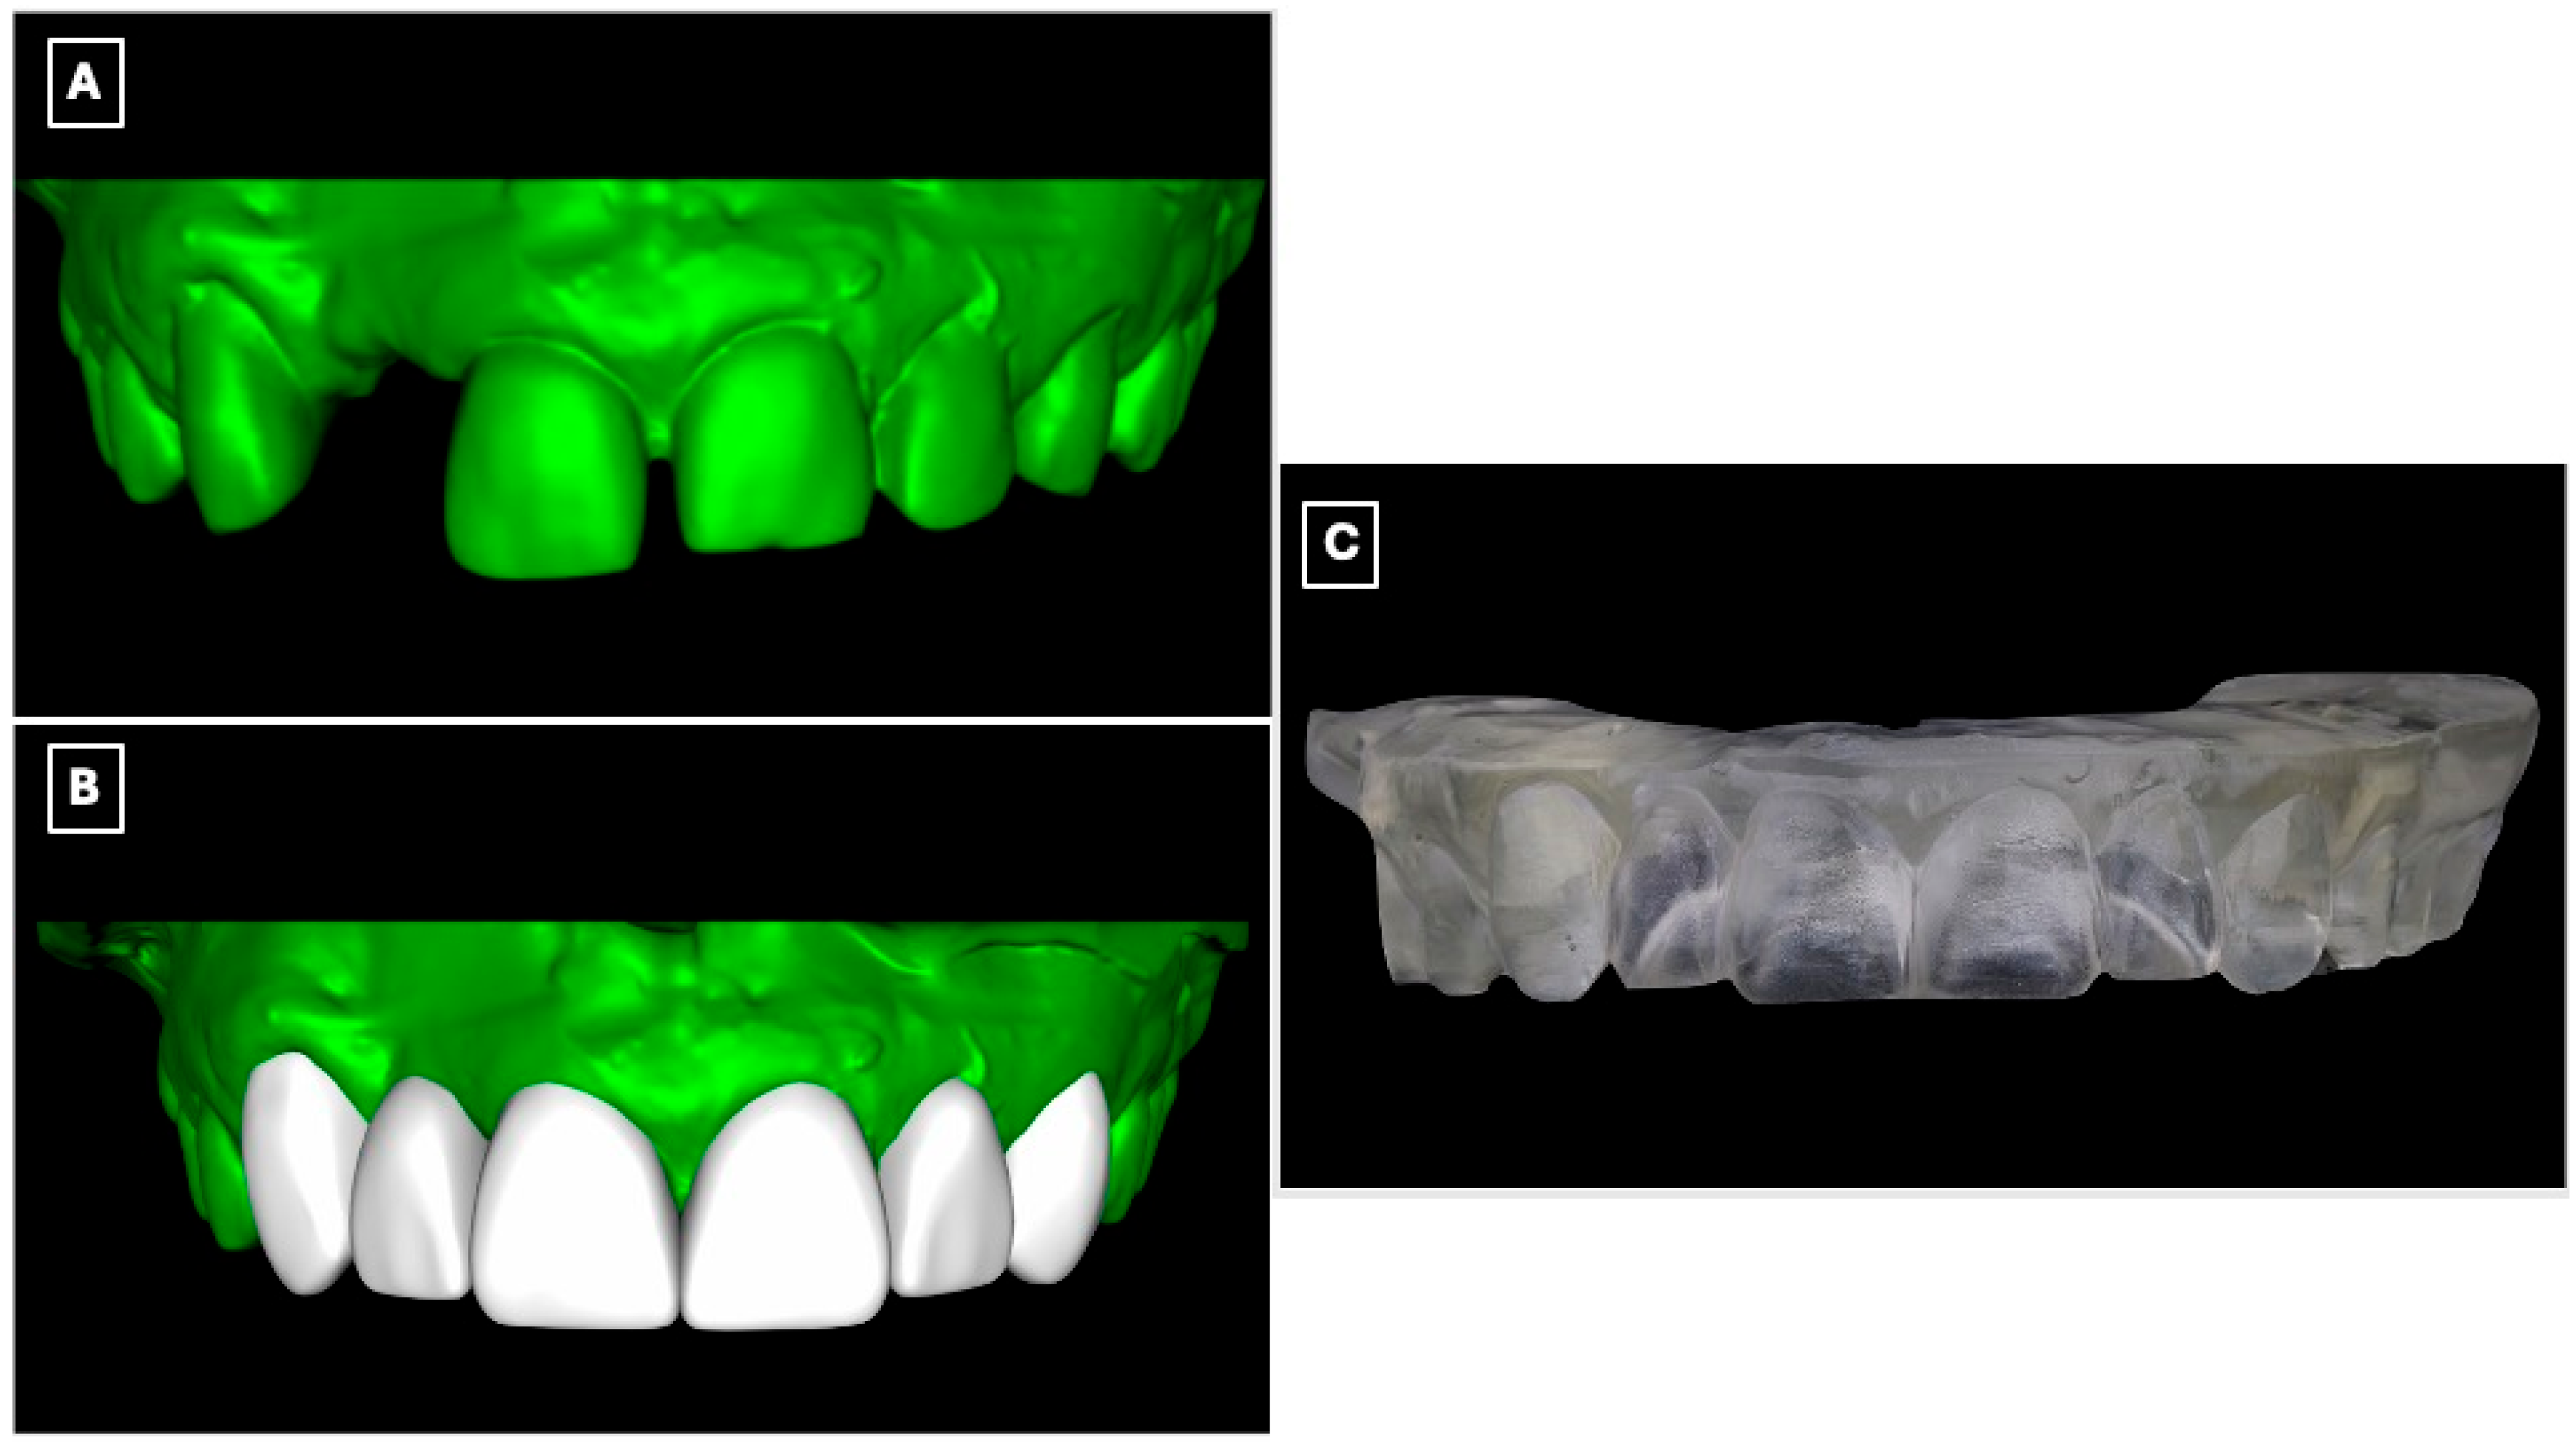

Diagnostic records were obtained, including preliminary impressions, and diagnostic casts were fabricated. The casts were digitized using an intraoral scanner (Medit i700, Medit Corp., Seoul, Republic of Korea) to enable a fully digital workflow (Figure 2A). A digital wax-up was subsequently designed based on esthetic, functional, and occlusal parameters (Figure 2B), allowing three-dimensional evaluation of tooth proportions, pontic position, and incisal edge relationships relevant to a minimally invasive adhesive prosthetic approach. The approved digital wax-up was then fabricated using a three-dimensional printer (NextDent 5100, NextDent B.V., Soesterberg, The Netherlands) to produce a physical diagnostic model for clinical reference and transfer of the digital plan to the operative phase (Figure 2C).

Figure 2.

Digital workflow used for diagnostic evaluation and prosthetic planning of the maxillary anterior region. (A) Digitized diagnostic cast obtained from preliminary impressions, allowing three-dimensional assessment of tooth position, edentulous space morphology, and enamel contours relevant to adhesive prosthesis design. (B) Virtual model following digital processing and wax-up, illustrating the planned tooth proportions, pontic position, and incisal edge relationships used to guide minimally invasive tooth preparation and prosthesis design. (C) Three-dimensionally printed diagnostic cast derived from the digital wax-up, used as a physical reference for mock-up fabrication and to facilitate accurate transfer of the digital plan to the clinical setting.

A silicone putty index (Express™ STD Putty, 3M ESPE, St. Paul, MN, USA) was fabricated from the printed diagnostic wax-up, and an intraoral mock-up was performed using a bis-acryl provisional material (Protemp™ 4, 3M ESPE, St. Paul, MN, USA) (Figure 3A). The mock-up enabled clinical evaluation of tooth proportions, incisal edge position, and smile integration, and served as a communication tool to confirm esthetic acceptance with the patient before performing any irreversible procedures.

Digital wax-up used for esthetic analysis and prosthetic planning of the anterior rehabilitation. (A) Virtual representation of the maxillary anterior region before wax-up, serving as a baseline for evaluating tooth position, incisal edge discrepancies, and space availability for the planned resin-bonded fixed dental prosthesis. (B) Digital wax-up design illustrating the proposed single-retainer cantilever resin-bonded fixed dental prosthesis and laminate veneers, with idealized tooth proportions, incisal edge position, and symmetry used to guide enamel-confined tooth preparation, pontic emergence profile, and overall esthetic integration within the smile.

Tooth preparation was performed under mock-up guidance to ensure minimal enamel reduction and to create optimal enamel-bonding surfaces (Figure 3B). Final impressions were obtained using a polyvinyl siloxane impression material (Imprint™ 4 PVS, 3M ESPE, St. Paul, MN, USA) and submitted to the dental laboratory for definitive fabrication.

Beyond its role in visualization, the digital wax-up and intraoral mock-up contributed directly to clinical decision-making and execution. The digitally planned wax-up enabled precise control of tooth proportions, incisal edge position, and pontic emergence profile, facilitating enamel-confined preparation and preservation of sound tooth structure. The intraoral mock-up functioned as a reduction guide during tooth preparation, minimizing unnecessary enamel removal and reducing chairside adjustments at the time of prosthesis seating. This digital-to-clinical transfer enhanced treatment predictability by allowing preoperative verification of esthetics and function, thereby improving clinical efficiency and patient acceptance.